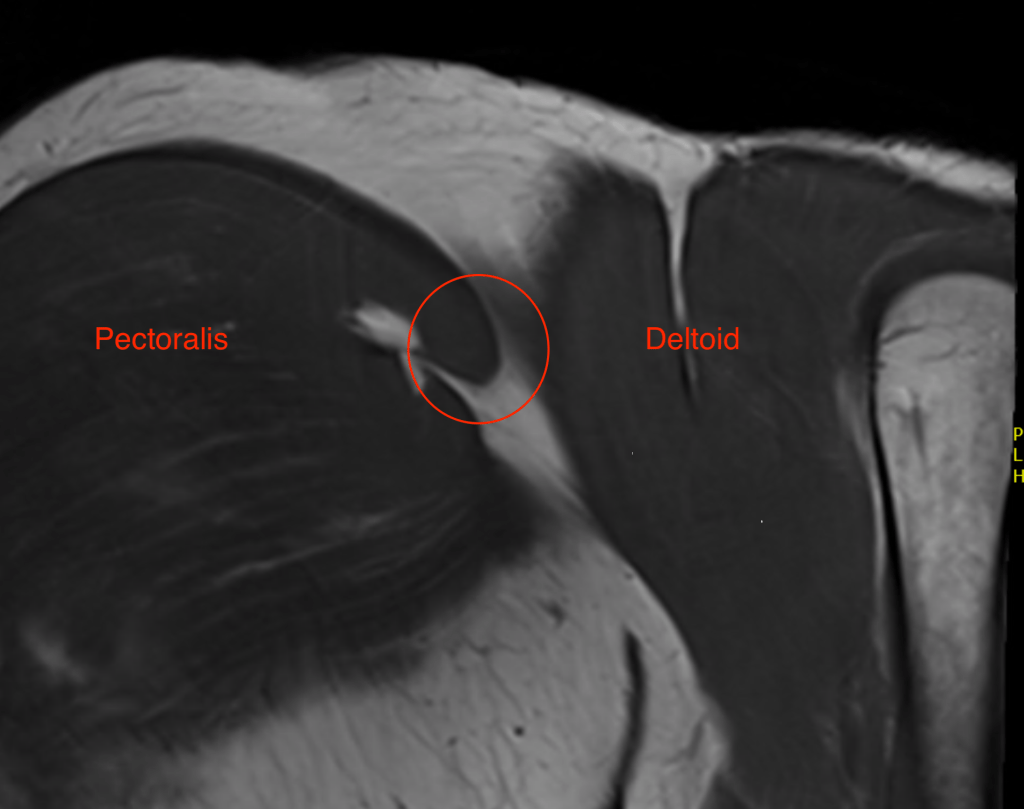

Pectoralis major tears

Patients can sometimes tear their pectoralis major muscle, often when doing bench press at the gym. This injury is often associated with a tearing sensation, pain, and bruising and swelling. This injury can be missed.

Clinical examination is usually good a identifying when this injury has occurred. Surgery can be indicated to fix the pectoralis tendon tear, especially when the tear is significant, and torn off the bone. However, sometimes the tear occurs at the area where the muscle attaches to the tendon, which is not easy or reliable to fix. For this reason, getting an urgent MRI can be very helpful, although the MRI is not always accurate.